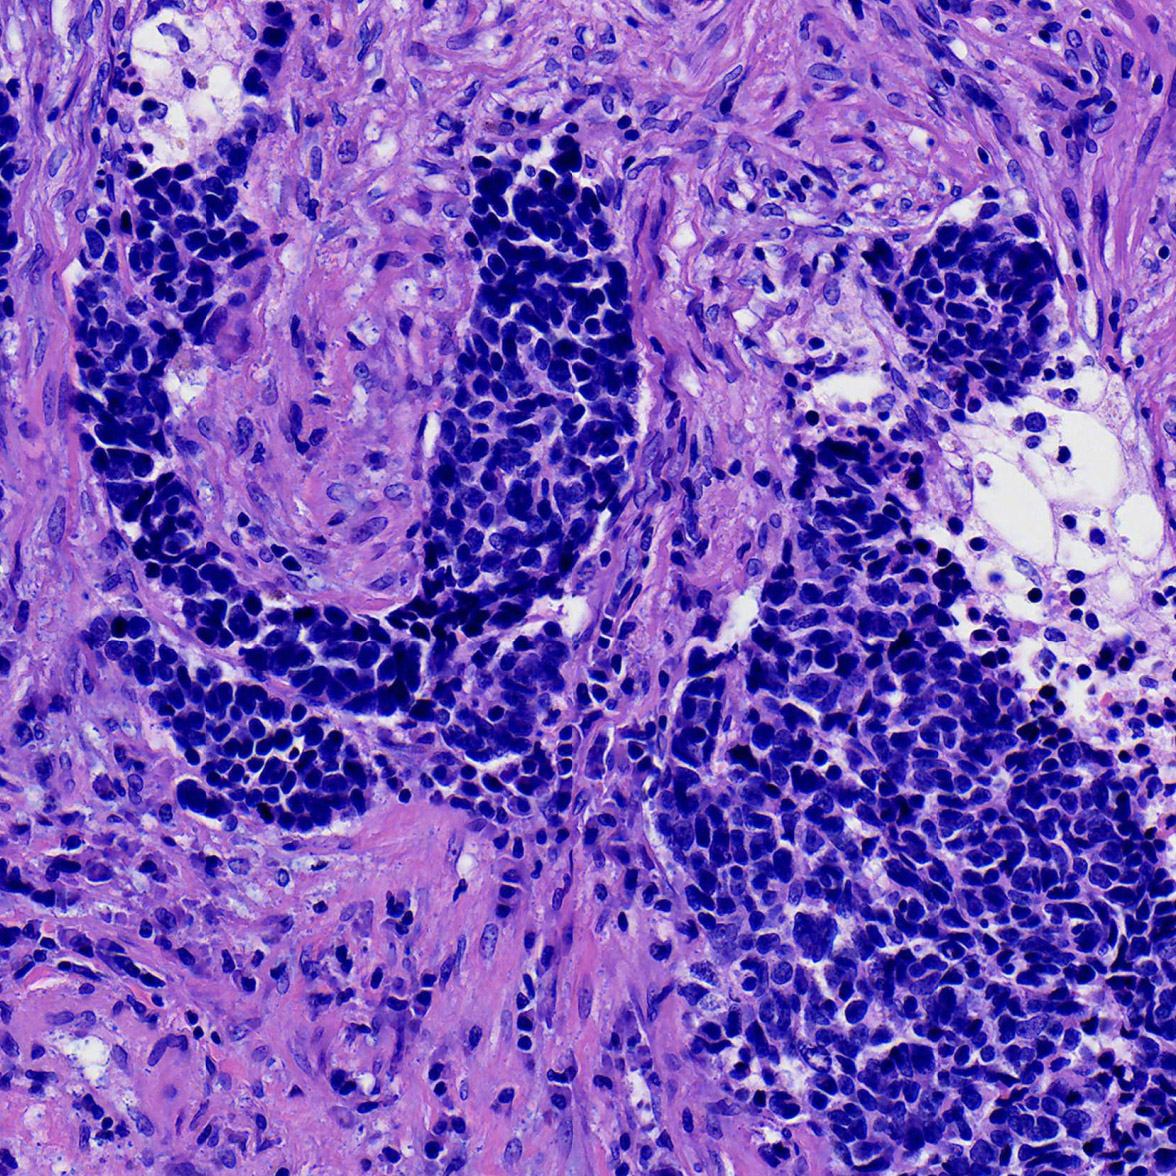

We use genomics, molecular & cellular biology, and genetically engineered mouse models to address important outstanding questions in the molecular oncology of breast and other solid tumors. Our team has a strong research focus in precision oncology and contributes to Wisconsin's statewide Precision Medicine Molecular Tumor Board.

Paraic Kenny is the Director of the Kabara Cancer Research Institute of the Gundersen Medical Foundation, and is a Clinical Adjunct Associate Professor of Medicine at the University of Wisconsin School of Medicine and Public Health in Madison and an Adjunct Associate Professor of Biology at the University of Wisconsin - La Crosse. The KCRI also houses the CAP-accredited Gundersen Cancer Biobank with more than 25,000 solid tumor specimens. -------- We gratefully acknowledge grant support from the following: